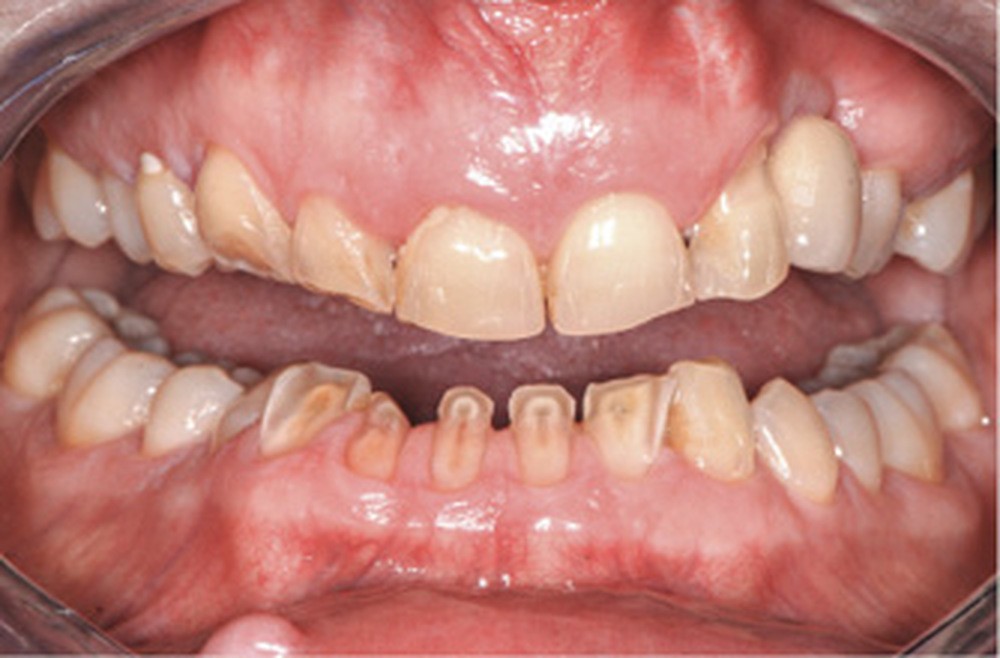

- l’usure particulière des dents du bloc incisivo-canin mandibulaire (fig. 2) ;

Certaines dents antérieures mandibulaires sont réduites pratiquement jusqu’à la…